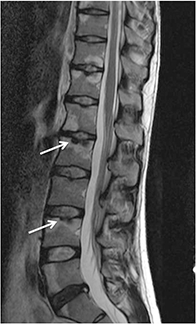

La espondilitis (Imagen 2) predomina en los hombres y se manifiesta por dolor lumbar que con frecuencia abarca ambas nalgas, de inicio insidioso, que mejora con el ejercicio y empeora con el reposo (con un dolor nocturno característico que muchas veces despierta al que lo padece) y que se acompaña de rigidez matutina. Aunque éste es el síntoma predominante de la enfermedad, también puede afectar a articulaciones periféricas (especialmente caderas, hombros y rodillas).

A diferencia de lo que suele suceder en la artritis, la espondilitis evoluciona de forma independiente a la EII y las manifestaciones clínicas no se relacionan ni con los períodos de remisión o exacerbación, ni con la localización o extensión de la enfermedad intestinal.

Además, el inicio de los síntomas axiales a menudo es generalmente independiente y suelen preceder a la enfermedad intestinal en varios años.